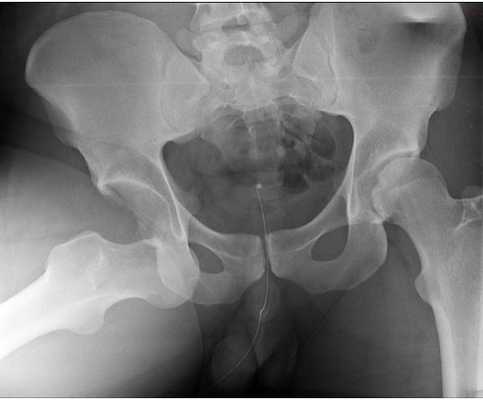

Снимок 2. Пациент обратился к врачу по поводу боли в правом паху и правом бедре, возникающей только при ходьбе или вставании со стула.

Коксартроз 2-й стадии. Фотография из архива доктора Евдокименко

В результате пациента 2 года (!) лечили от несуществующего остеохондроза. Но поскольку пациенту становилось только хуже, его, наконец, отправили на обследование. И провели, помимо прочего, рентген тазобедренных суставов. После получения рентгеновских снимков врачи наконец смогли (спустя 2 года) поставить правильный диагноз: «коксартроз».

Вот что мы видим на снимке пациента:

- головка бедренной кости «подтянулась» к вертлужной впадине, расстояние между костями совсем небольшое (уменьшение размеров суставной щели). Это говорит о том, что суставной хрящ, покрывающий сочленяющиеся части костей, стал гораздо тоньше (как вы помните, на рентгене сам хрящ не виден);

- оставшись без «хрящевого амортизатора», головка бедренной кости стала деформироваться, частично расплющиваться. Она теперь не такая идеально-круглая, как должна быть.

Такие рентгенологические изменения соответствуют коксартрозу второй стадии.